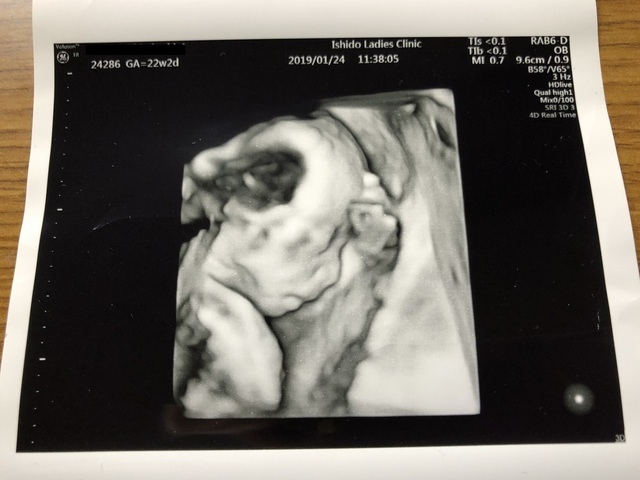

22週3日(22w3d・男の子)|N氏 さん(26歳)

エコー写真撮影時のエピソード:

今回、初めての子で4Dエコーをしてもらって、この時旦那さんも一緒だったんですが、顔を見せてくれてとてもかわいいし、愛おしく思いました。

この時に性別も男の子かも?と言われて、旦那さんは男の子希望だったので喜んでいました。 あんなに小さかった子が大きくなって、 今は人間らしい姿になっていて、 ほんとに凄いなと感激しました。

私は正直、女の子希望だったのですが、 母子ともに健康で生まれてきてくれればどちらでもいいと思いましたし、 私達の子どもにはかわりないので今は早く会いたいなと毎日胎動を感じながら、日々を過ごしています。

両親、兄姉、親戚、皆楽しみにしてくれているので残り少ないマタニティライフを楽しみつつ、旦那さんとの2人の時間を大切にして、出産にのぞみたいと思っています。 それまで準備などをして、我が子の誕生を待ちたいと思ってます。